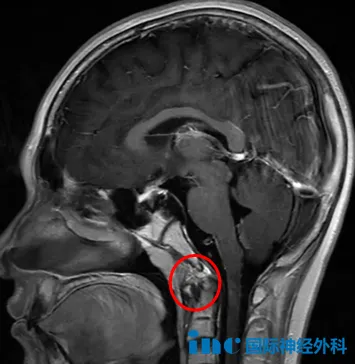

更加不幸的是,今年小海的头痛突然加重了,这一次,他终于见到了脑瘤的“真面目”——颅底斜坡区一个33×26×33mm的大肿瘤,已经侵袭左侧海绵窦,导致垂体移位,就连垂体柄都已被推歪。医生高度怀疑这是一个脊索瘤。

脊索瘤,一听小海患上的可能是这个罕见肿瘤,父母的心顿时沉了下去。这是一种手术全切极其困难、复发率高、手术风险极大的肿瘤。而小海的肿瘤恰好位于斜坡,这里处在颅底中央,紧邻脑干、基底动脉、颅神经、垂体及海绵窦,关系到患儿的生命、神经、内分泌调节和传导等重要神经功能,任何一处的手术损伤,都可能引起重大的神经功能障碍!

此外,由于手术可操作的空间极其狭小,也更容易残留肿瘤,切不完不说,术后孩子更可能出现偏瘫、复视、面瘫、脑脊液漏等并发症,可以说,手术一旦有丝毫失误,小海的一生都可能被毁掉。

术后,小海的恢复始终良好,在四个月后的随访中,福教授表示:“MRI结果在我看来非常理想,鼻腔结构完全正常,我未见明显的肿瘤残留。”